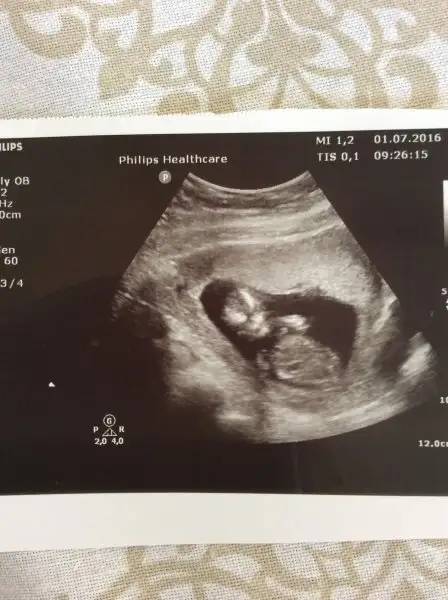

Merhabalar ben de yorum bekliyorum, ilk kese hali ve 12+6 daki hali. Dün doktordaydım göstermedi kendini kuzum.Havalianne__ yorumunu merak ediyorum canım

Doktor kıza benziyor dedi ama ben de içimden erkek geçiriyorum :) neyse sağlıklı ve hayırlısı olsun da tek önemli olan bu.Erkek gibi

Hadi hayırlısı teşekkür ederim canım :)Plasenta solda bebekte sola yatkın erkek gibi

Hayırlısı ile inşallah bakalımUsg karındansa erkek gibi,vajinalsa kız gibi cnm